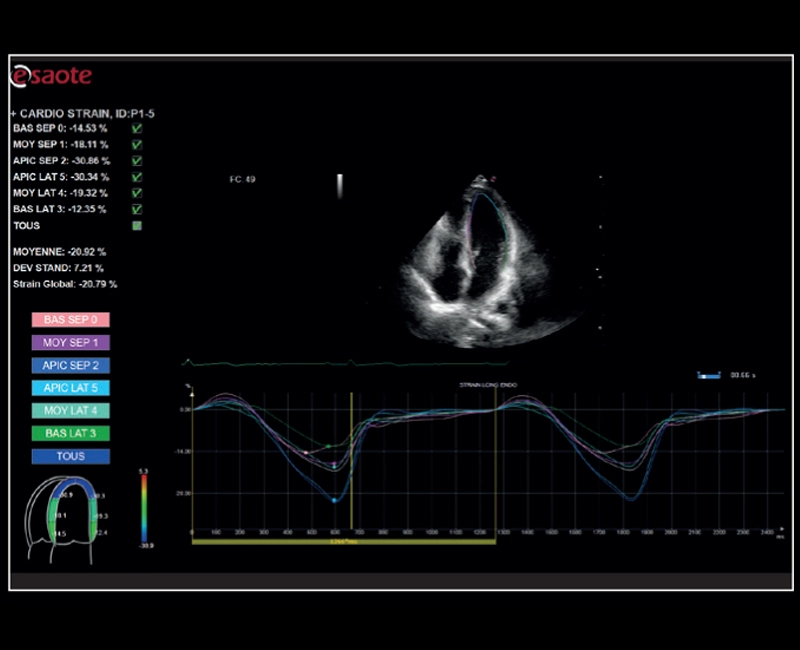

MyLab™Sigma - Left Ventricle XStrain 2D analysis

MyLab™Sigma - Left Ventricle XStrain 2D analysis